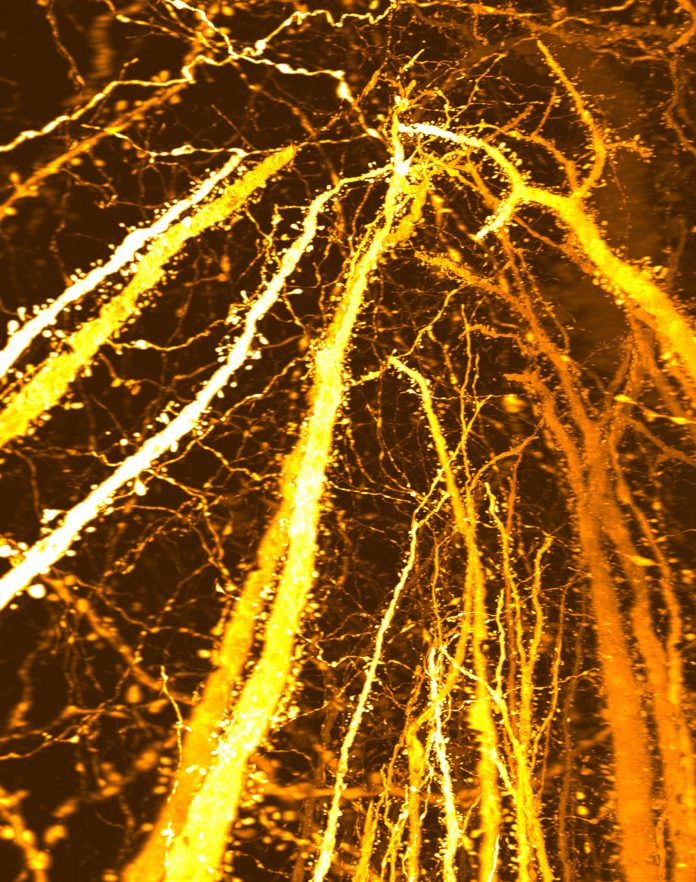

Η εφηβεία θεωρείται ευρέως ότι είναι μια περίοδος κατά την οποία ο εγκέφαλος κόβει τις υπερβολικές νευρικές συνδέσεις, βελτιώνοντας τα κυκλώματα μέσω συναπτικού κλαδέματος. Νέα έρευνα δείχνει τώρα ότι αυτή η άποψη μπορεί να είναι ελλιπής. Η εφηβεία είναι όταν το «κέντρο ελέγχου» του εγκεφάλου συνεχίζει να έρχεται στο διαδίκτυο. Καθώς οι έφηβοι προχωρούν προς την ενηλικίωση, δεξιότητες όπως ο προγραμματισμός μπροστά, η στάθμιση των συνεπειών και η επίλυση άγνωστων προβλημάτων […]

Νέα Προκλήσεις Ανακάλυψης Εγκεφάλου Η μακροχρόνια θεωρία της ανάπτυξης του εγκεφάλου των εφήβων